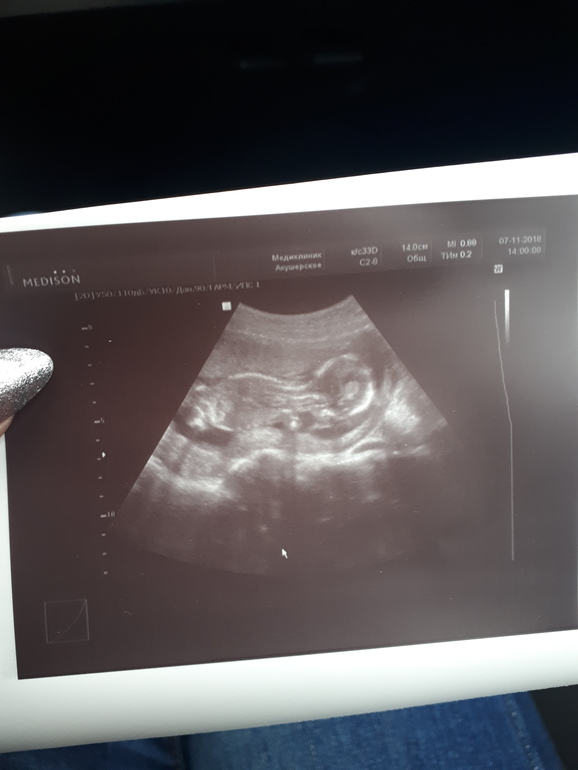

Ольга Горячева 7 лет 19ая неделя Давно что-то я тут ничего не писала... Снова возвращаюсь😅 Сейчас я на 19й неделе, время летит очень быстро. Стало известно, что ждем девочку 🤗 Посмотрите еще 20 записей на эту тему Отменить Ответить И снова тест и снова две полоски! Долгожданное УЗИ Чаты Беременных Выберите чат: Январята-2026 Февралята-2026 Мартята-2026 Апрелята-2026 Майчата-2026 Июнята-2026 Июлята-2026 Августята-2026